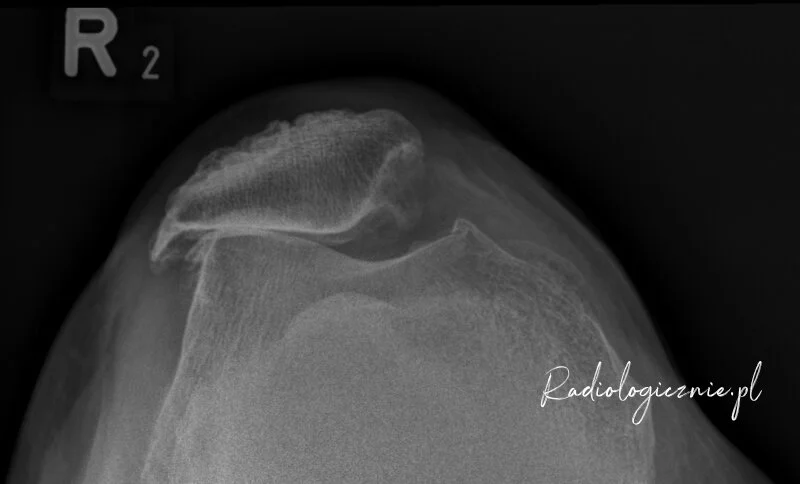

Obraz RTG nasilonych zmian zwyrodnieniowych ze zniesieniem / zwężeniem szpary stawowej. Dodatkowo widoczne osteofity krawędzi stawowych